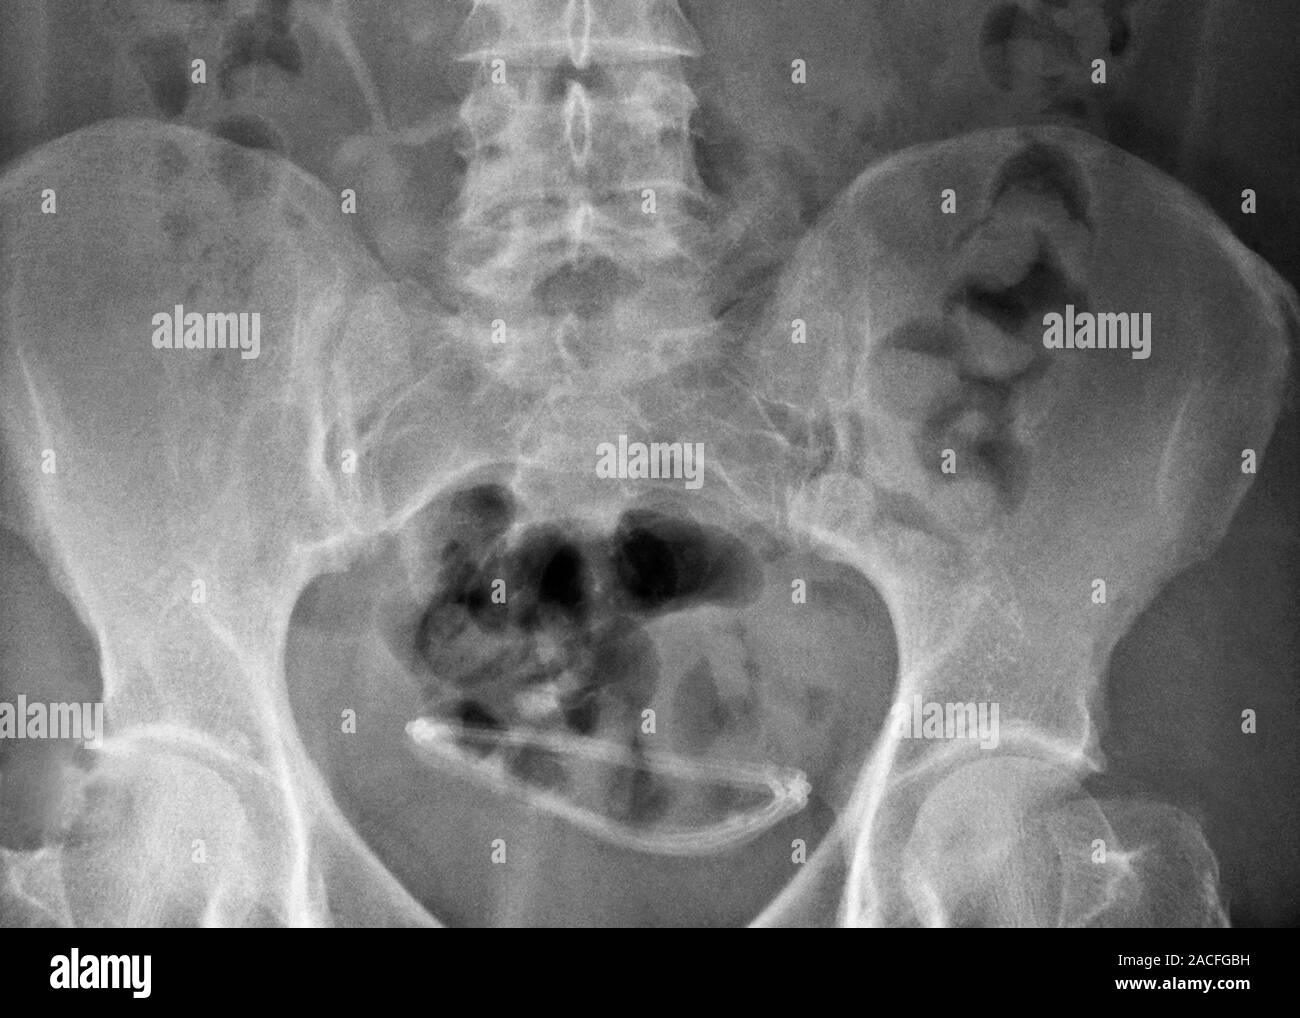

Ectopic hydrocephalic shunt. Xray of the pelvis of a patient, showing X Ray Ectopic Pregnancy Read this article to learn more about…. In an ectopic pregnancy, the fertilised egg gets stuck, most often in the fallopian tubes. An adnexal mass that is separate from the ovary and the tubal ring sign are the most common findings of a tubal pregnancy. The fallopian tube is the most common location for an ectopic pregnancy. Suspect ectopic pregnancy. X Ray Ectopic Pregnancy.

Ectopic IUD contraceptive, Xray Stock Image F008/3473 Science X Ray Ectopic Pregnancy An adnexal mass that is separate from the ovary and the tubal ring sign are the most common findings of a tubal pregnancy. In an ectopic pregnancy, the fertilised egg gets stuck, most often in the fallopian tubes. There are several types of eps:. Suspect ectopic pregnancy in any female of reproductive age with pelvic pain, vaginal bleeding, or unexplained. X Ray Ectopic Pregnancy.